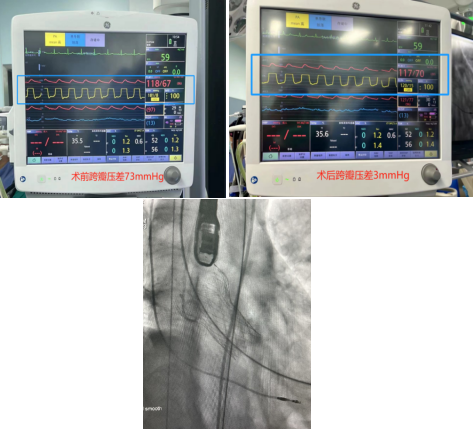

患者是一位68岁女性,因“反复活动后胸闷3年,加重1周”入院。心脏彩超提示存在主动脉瓣二叶畸形合并重度狭窄,诊断为主动脉瓣重度狭窄。患者因存在横位心、心肌肥厚,左室容积小和较小的主动脉弓角等问题,使得手术操作更为复杂。独墅湖医院专家团队综合考虑后决定行TAVR手术。患者术前跨瓣压差测得73mmHg左右,术后即刻跨瓣压差小于3mmHg,手术顺利,患者胸闷症状明显改善。本次手术由独墅湖医院副院长、心血管内科周亚峰教授,赵良平主任医师以及陈弹主任医师带领的多学科协作诊疗(MDT)团队完成。